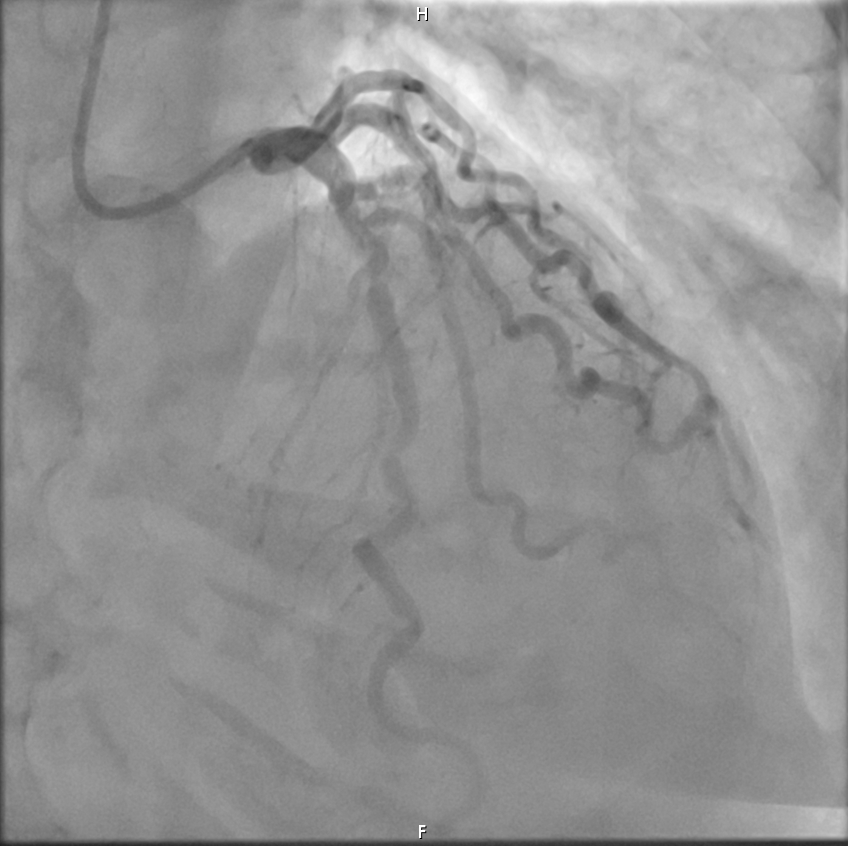

En la sala de hemodinámica se realiza en primer lugar cateterismo coronario hallándose estenosis de 70% del segmento medio de la arteria coronaria Descendente Anterior (DA). A través de Intervención Coronaria Percutánea se implanta stent farmacoactivo con buen resultado final.

Síndrome de Tako-Tsubo activado como código IAM + Enfermedad coronaria de 1 vaso: descendente anterior media (70%).